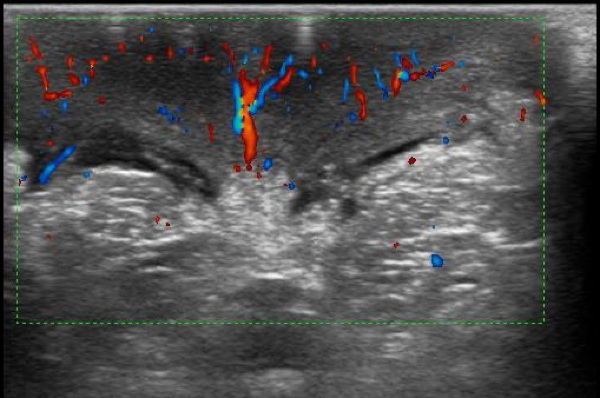

Manuel � un ragazzino di otto anni, che viene portato in Pronto Soccorso per la comparsa da alcune ore di una tumefazione scrotale, accompagnata da una vaga dolenzia localizzata. Non � presente una storia di traumi, febbre o disuria. Obiettivamente lo scroto si presenta iperemico e tumefatto bilateralmente, anche se in maniera asimmetrica, senza interessamento del pene, dell'inguine o del perineo (Figura 1). I testicoli sono palpabili ma tale manovra provoca un vivo dolore; i riflessi cremasterici non sono evocabili e la transilluminazione scrotale risulta negativa. Figura 1. Scroto iperemico e tumefatto, in caso di edema scrotale. Figura 2. Ecografia scrotale: importante ispessimento del tessuto cutaneo-sottocutaneo. Figura 3. Ecografia color-doppler del paziente. Figura 4. Ecografia color-doppler che mostra il �segno della fontana� dato dall�aumento del flusso sanguigno nella pelle scrotale edematosa (da voce bibliografica 1).

Un'ecografia scrotale (Figura 2), richiesta in urgenza per escludere una possibile torsione, ha mostrato entrambi i testicoli in posizione pi� alta che di norma, con volume regolare e vascolarizzazione conservata, senza lesioni focali. Il reperto dirimente � stato per� il riscontro di un importante ispessimento del tessuto cutaneo-sottocutaneo scrotale, con intensa iperemia nella valutazione con il color-doppler che nelle sezioni trasverse disegnava l'immagine di una �fontana scrotale� (Figure 3 e 4), suggestiva di Edema Scrotale Acuto Idiopatico (AISE). La negativit� degli indici di flogosi ha escluso con certezza che potesse trattarsi di una cellulite in fase iniziale.

L'AISE � una condizione benigna, una dermatosi, a cui fa capo, secondo la letteratura, dal 3% al 20% di tutti i casi di scroto acuto. Si tratta di una diagnosi di esclusione di altre patologie per cui un intervento si rende immediato, prima fra tutte la torsione testicolare. L'ecografia � l'ausilio diagnostico pi� importante a tale scopo e la valutazione con color-doppler pu� evidenziare il �segno della fontana�, immagine caratteristica data dall'incrementato flusso sanguigno all'interno dei tessuti molli peritesticolari.